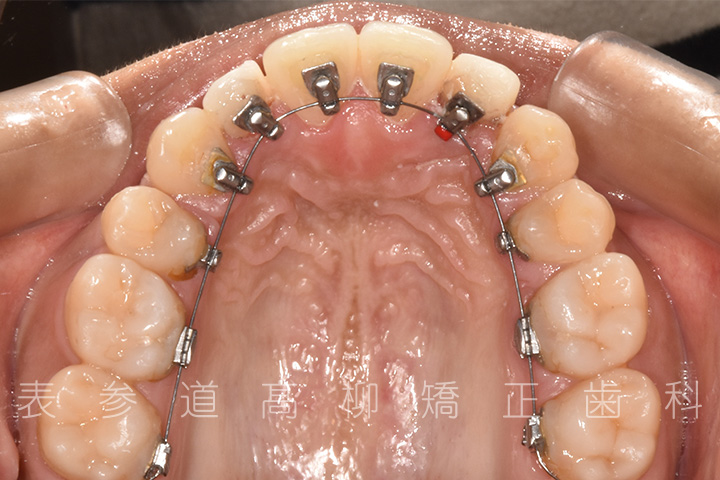

• 矯正治療開始

・リンガルブラケット装置

・歯科矯正用アンカースクリュー

・アライナー